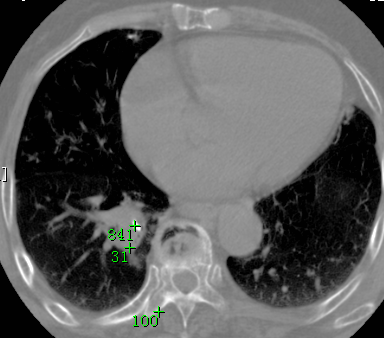

标题: CT26680:肺部右下肺静脉干结节的界定 [打印本页]

标题: CT26680:肺部右下肺静脉干结节的界定

考虑1、周围型肺癌,2肺静脉畸形,前者可能大,建议增强检查。

考虑1、周围型肺癌,2肺静脉畸形,前者可能大,建议增强检查。支持!

中心型肺癌,纤支镜可帮助明确。